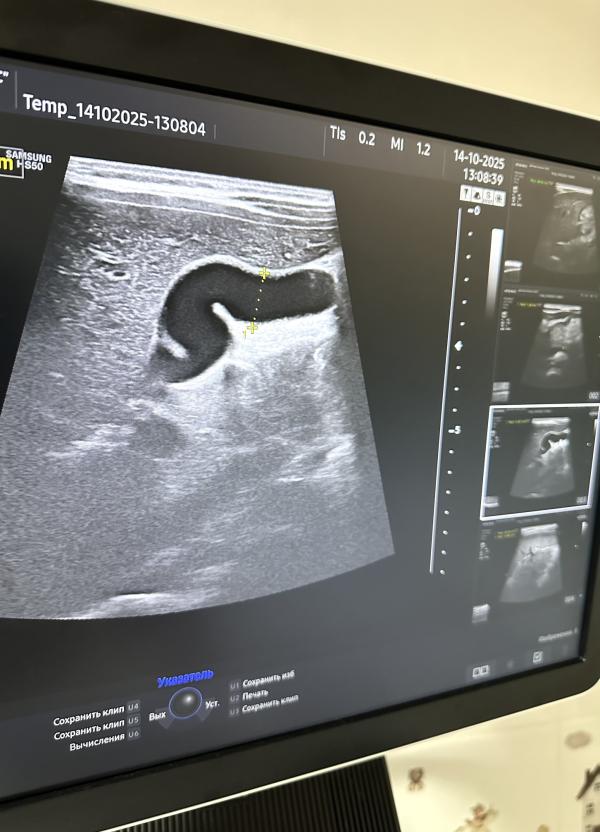

Желчный пузырь — небольшой мешочек, расположенный под печенью, предназначенный для хранения жёлчи, вырабатываемой печенью. Форма желчного пузыря обычно грушевидная, овальная или округлая. Иногда форма может меняться, приобретая перегибы, перетяжки или дополнительные складки. Такое явление называют деформацией желчного пузыря.

- Перегиб шейки желчного пузыря;

- Формирование перегородок внутри органа.

*на сканах представлены разные желчные пузыри

Пока в просвете желчного пузыря отсутствуют признаки патологических изменений, таких как наличие желчи, конкрементов (камней) или новообразований, поводов для беспокойства нет